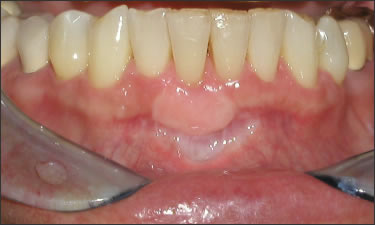

This mouth had recession on just one tooth with very little bone to support the tooth. The area needed support and thickness. The tissue was placed and the area now has thicker tissue to withstand the forces that the patient needs to place on it.